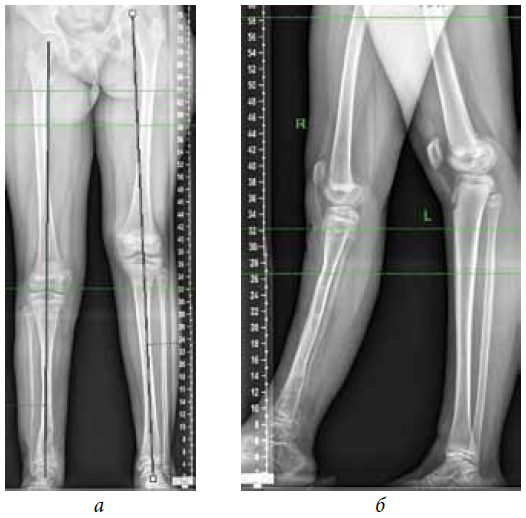

The second stage of treatment was the recommended correction of the resulting multiplane deformities of the affected lower extremity (mMPTA was 94°, mLDTA was 71°, aPPTA was 90°, and aADTA was 59°, shortening the affected lower limb by 8.0 cm). For lengthening and deformity correction of the right lower limb, the patient underwent preoperative planning for deformity correction with the exception of osteotomies in the area of consolidated pseudoarthrosis at the age of 9 years. According to the plan, a two-level osteotomy of the shin bones was performed, as along with lengthening by 5 cm by the Ilizarov method. The deformity was corrected using a repositional unit with Ortho-SUV computer navigation properties. The period of deformity correction was 58 days, and the external fixation period was 247 days. At the end of the fixation period, a recurrence of deformities of the tibial bones was detected with the formation of a deformity apex at the level of the proximal and distal tibial growth zones (mMPTA was 94°, mLDTA was 82°, aPPTA was 86°, and aADTA was 80°) (Fig. 1–4). We applied hemiepiphysiodesis to correct the recurrence of valgus deformity of the tibia. The period of deformity correction was 269 days. The reference angles values of the tibia were within the accepted ranges.

Fig. 7. Radiographs of the patient after removing the plate and screws according to hemiepiphysiodesis: а — anterior-posterior view; b — lateral view